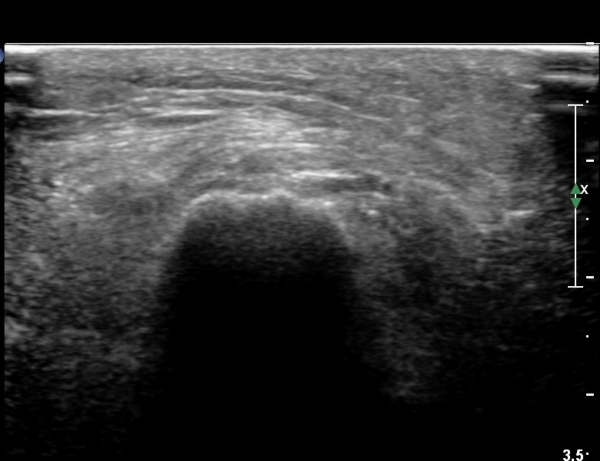

ŽÃËÀÚ¸¦ Á» ´õ ¸»´ÜÀ¸·Î À̵¿ÇÏ´Ï ºñ°ñ °æºÎ Ç¥Ãþ¿¡¼­ ºñ°ñ½Å°æÀÌ °üÂûµÇ°í(»çÁø 6, 7),